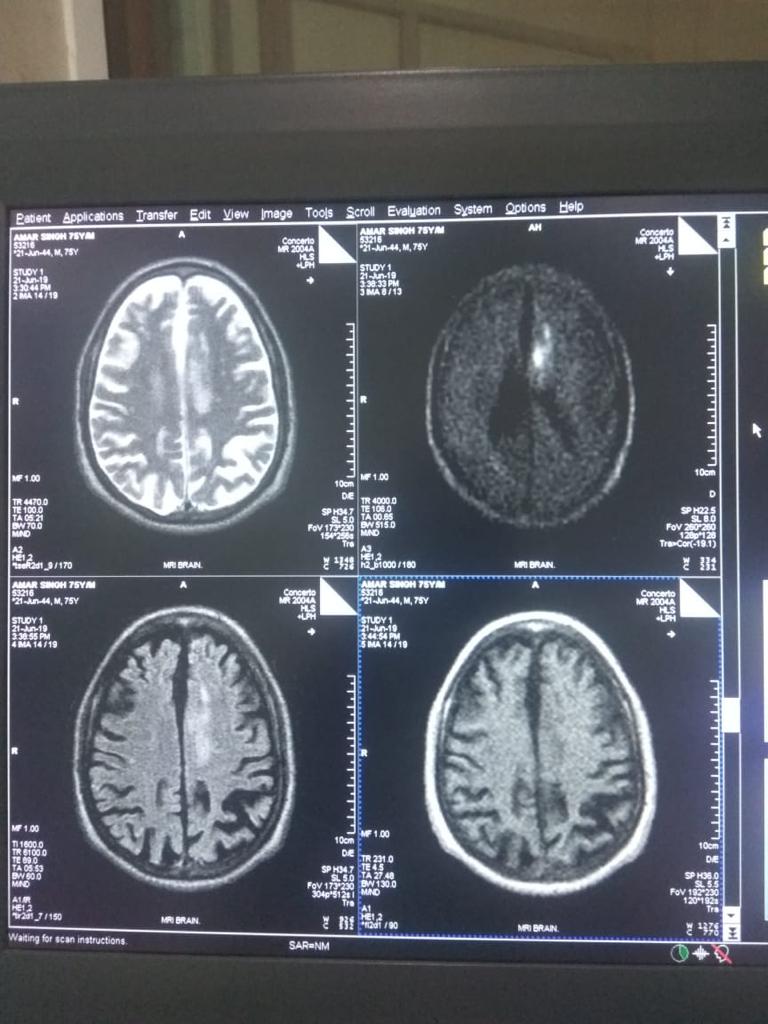

Cases